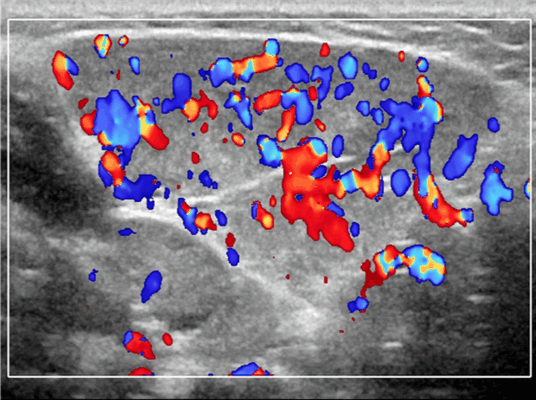

Лучшая диагностическая подсказка. Четко выраженная опухоль с диффузной гиперваскуляризацией внутри очага поражения / интенсивным усилением кровотока на УЗИ с ЦДК. Сосуды внутри и рядом с образованием во время фазы пролиферации (ФП). Уменьшение размера за счет замещения жировой ткани во время фазы инволюции (ФИ)

Энергетический допплер. Отмеченный доплеровский сигнал потока на всем протяжении пораженных сосудов

Результаты ультразвукового исследования. УЗИ в серошкальном режиме. Большинство сосудистых венозных гемангиом (80%) выглядят неоднородно гипоэхогенными. Большие анэхогенные сосудистые пространства видны менее чем в 50% случаев, серпигинозные и синусоидальные. Поражения с небольшими сосудистыми каналами могут казаться эхогенными (из-за множества акустических границ, отражающих звук). Определить пределы образования бывает трудно, так как компоненты поражения могут быть изоэхогенными в околоушной паренхиме и незаметно смешиваться. Внутрипросветное движение эхо-сигналов при УЗИ в реальном времени, представляющее медленный сосудистый кровоток. Характерны эхогенные флеболиты с задним акустическим затенением. Сообщается, что они присутствуют только в 20% ВСМ. Иногда поражается вся околоушная железа, имитируя диффузную или инфильтративную патологию. Целесообразность склеротерапии оценивается соотношением сосудистых пространств к эхогенной матрице

Цветной допплер. Выраженный цветной доплеровский сигнал присутствует в областях, где поток значительный. Используйте фильтр для стенок сосудов и низкую частоту повторения импульсов (PRF) для увеличения доплеровской чувствительности. Отсутствует допплеровский сигнал при медленном кровотоке или тромбировании. Доплеровский сигнал потока изменяется различными маневрами. В поверхностных участках доплеровский сигнал может быть остановлен прямым сжатием датчика над поражением. Сигнал потока может иногда быть усилен маневром Вальсальвы или дистальным сжатием, но последнее трудно выполнить в области лица.